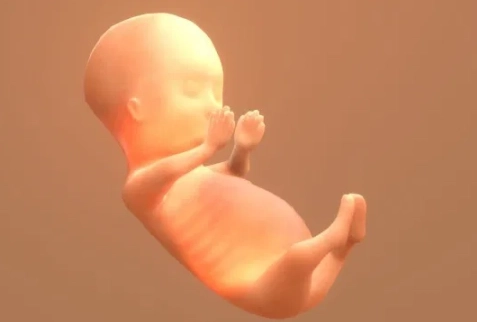

By 12 weeks, your little one is no longer an embryo but a full-fledged fetus. All the major organ systems are formed and are now busy growing and maturing. It's like the construction crew has finished the framework and is now installing the wiring and plumbing.

- Size: About the size of a lime or a plum, roughly 2 inches (5 cm) crown-to-rump.

- Key Features: Fingers and toes have separated and lost their webbed look. Tiny fingernails are starting to form. The eyes, which started out on the sides of the head, have moved closer together. The ears are almost in their final position.

- Movement: Oh, they're moving! Kicking, stretching, even making little fist clenches. You won't feel it for several more weeks, but on an ultrasound, it's a beautiful, wiggly sight.

- Organs: The kidneys are starting to produce urine (which becomes amniotic fluid), the bone marrow is making white blood cells, and the liver is secreting bile. The intestines, which grew partly in the umbilical cord, are moving into the abdomen.